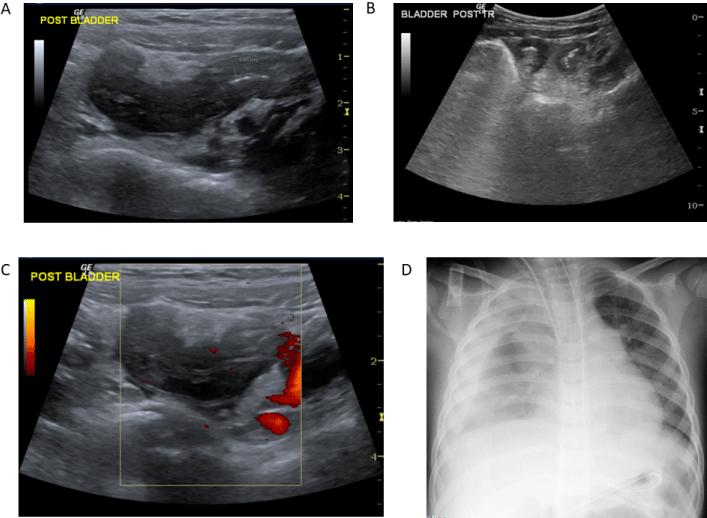

Article ID: wji.2026.b1901

De Novo Infection‑Associated Complement‑Mediated Hemolytic Uremic Syndrome in a Renal Transplant Recipient: A Complex Diagnostic Journey

Govani DR 1 Swamy KB 2 Mehta AR 3 Midha PK 4 Govani ND 1 Panchasara NG 1 Patel RR 1 Patel RV* 1

A 71‑year‑old renal transplant recipient presented with progressive malaise, gastrointestinal symptoms, fever, anemia, and acute graft dysfunction following recent travel abroad. Initial investigations revealed Micro‑Angiopathic Hemolytic Anemia (MAHA), thrombocytosis evolving into relative thrombocytopenia, elevated inflammatory markers, and declining renal function. The diagnostic process was complicated by overlapping possibilities including infection, viral reactivation, drug toxicity,…